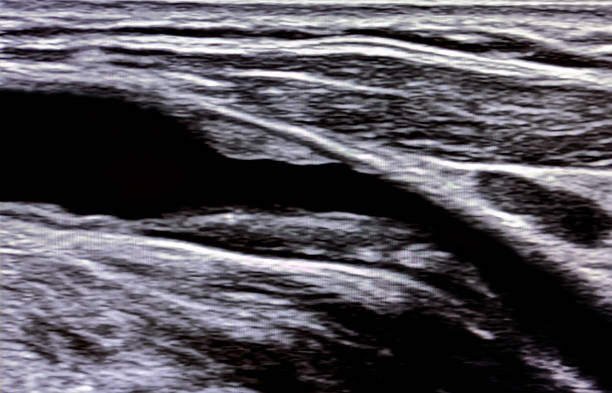

경동맥 초음파 검사는 초음파 기계를 사용하여 경동맥의 상태를 확인하는 검사입니다. 이 검사는 무해하고 비침습적이며, 빠르게 수행할 수 있어 환자에게 불편함을 주지 않습니다. 검사 과정은 다음과 같습니다.

- 환자는 안정된 자세로 앉거나 누워서 검사를 받습니다.

- 의사나 초음파 기술자는 초음파 젤을 사용하여 목 부위에 초음파 프로브를 적용합니다.

- 초음파 프로브는 고주파 소리파장을 방출하여 경동맥의 이미지를 생성합니다.

- 이미지를 컴퓨터 모니터에 표시하여 의사가 경동맥의 상태를 시각적으로 확인할 수 있습니다.